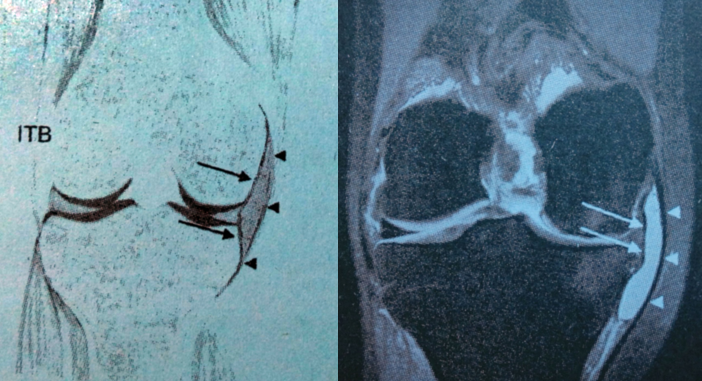

1.髂胫束囊

在髂胫束与股骨外上髁之间的滑囊,是用以润滑髂胫束的滑动,减少其与股骨的摩擦。髂胫束摩擦综合症(俗称跑步膝),跑步、骑车爱好者经常会出现膝关节外侧疼痛,痛感时轻时重,大腿完全弯曲或者完全伸直时痛感最强。

5.髂胫滑囊炎和腱鞘炎位于邻近Gerdy's结节的髂胫束止点的远端与胫骨表面附近,髂胫滑囊炎和腱鞘炎通常是因为过度使用,膝关节的足内翻压力,发生在训练坡面跑步运动员的腿下侧。髂胫滑囊炎引起前外侧膝关节疼痛,近似外侧半月板或外侧副韧带损伤。

MRI表现:边界清楚的液体聚积影,位于髂胫束韧带远端止点附近到胫骨前外侧面。髂胫束腱鞘炎有相近的临床表现,但是MRI显示在T1WI和T2WI上边界欠清的信号增高,以此可与滑膜炎鉴别。